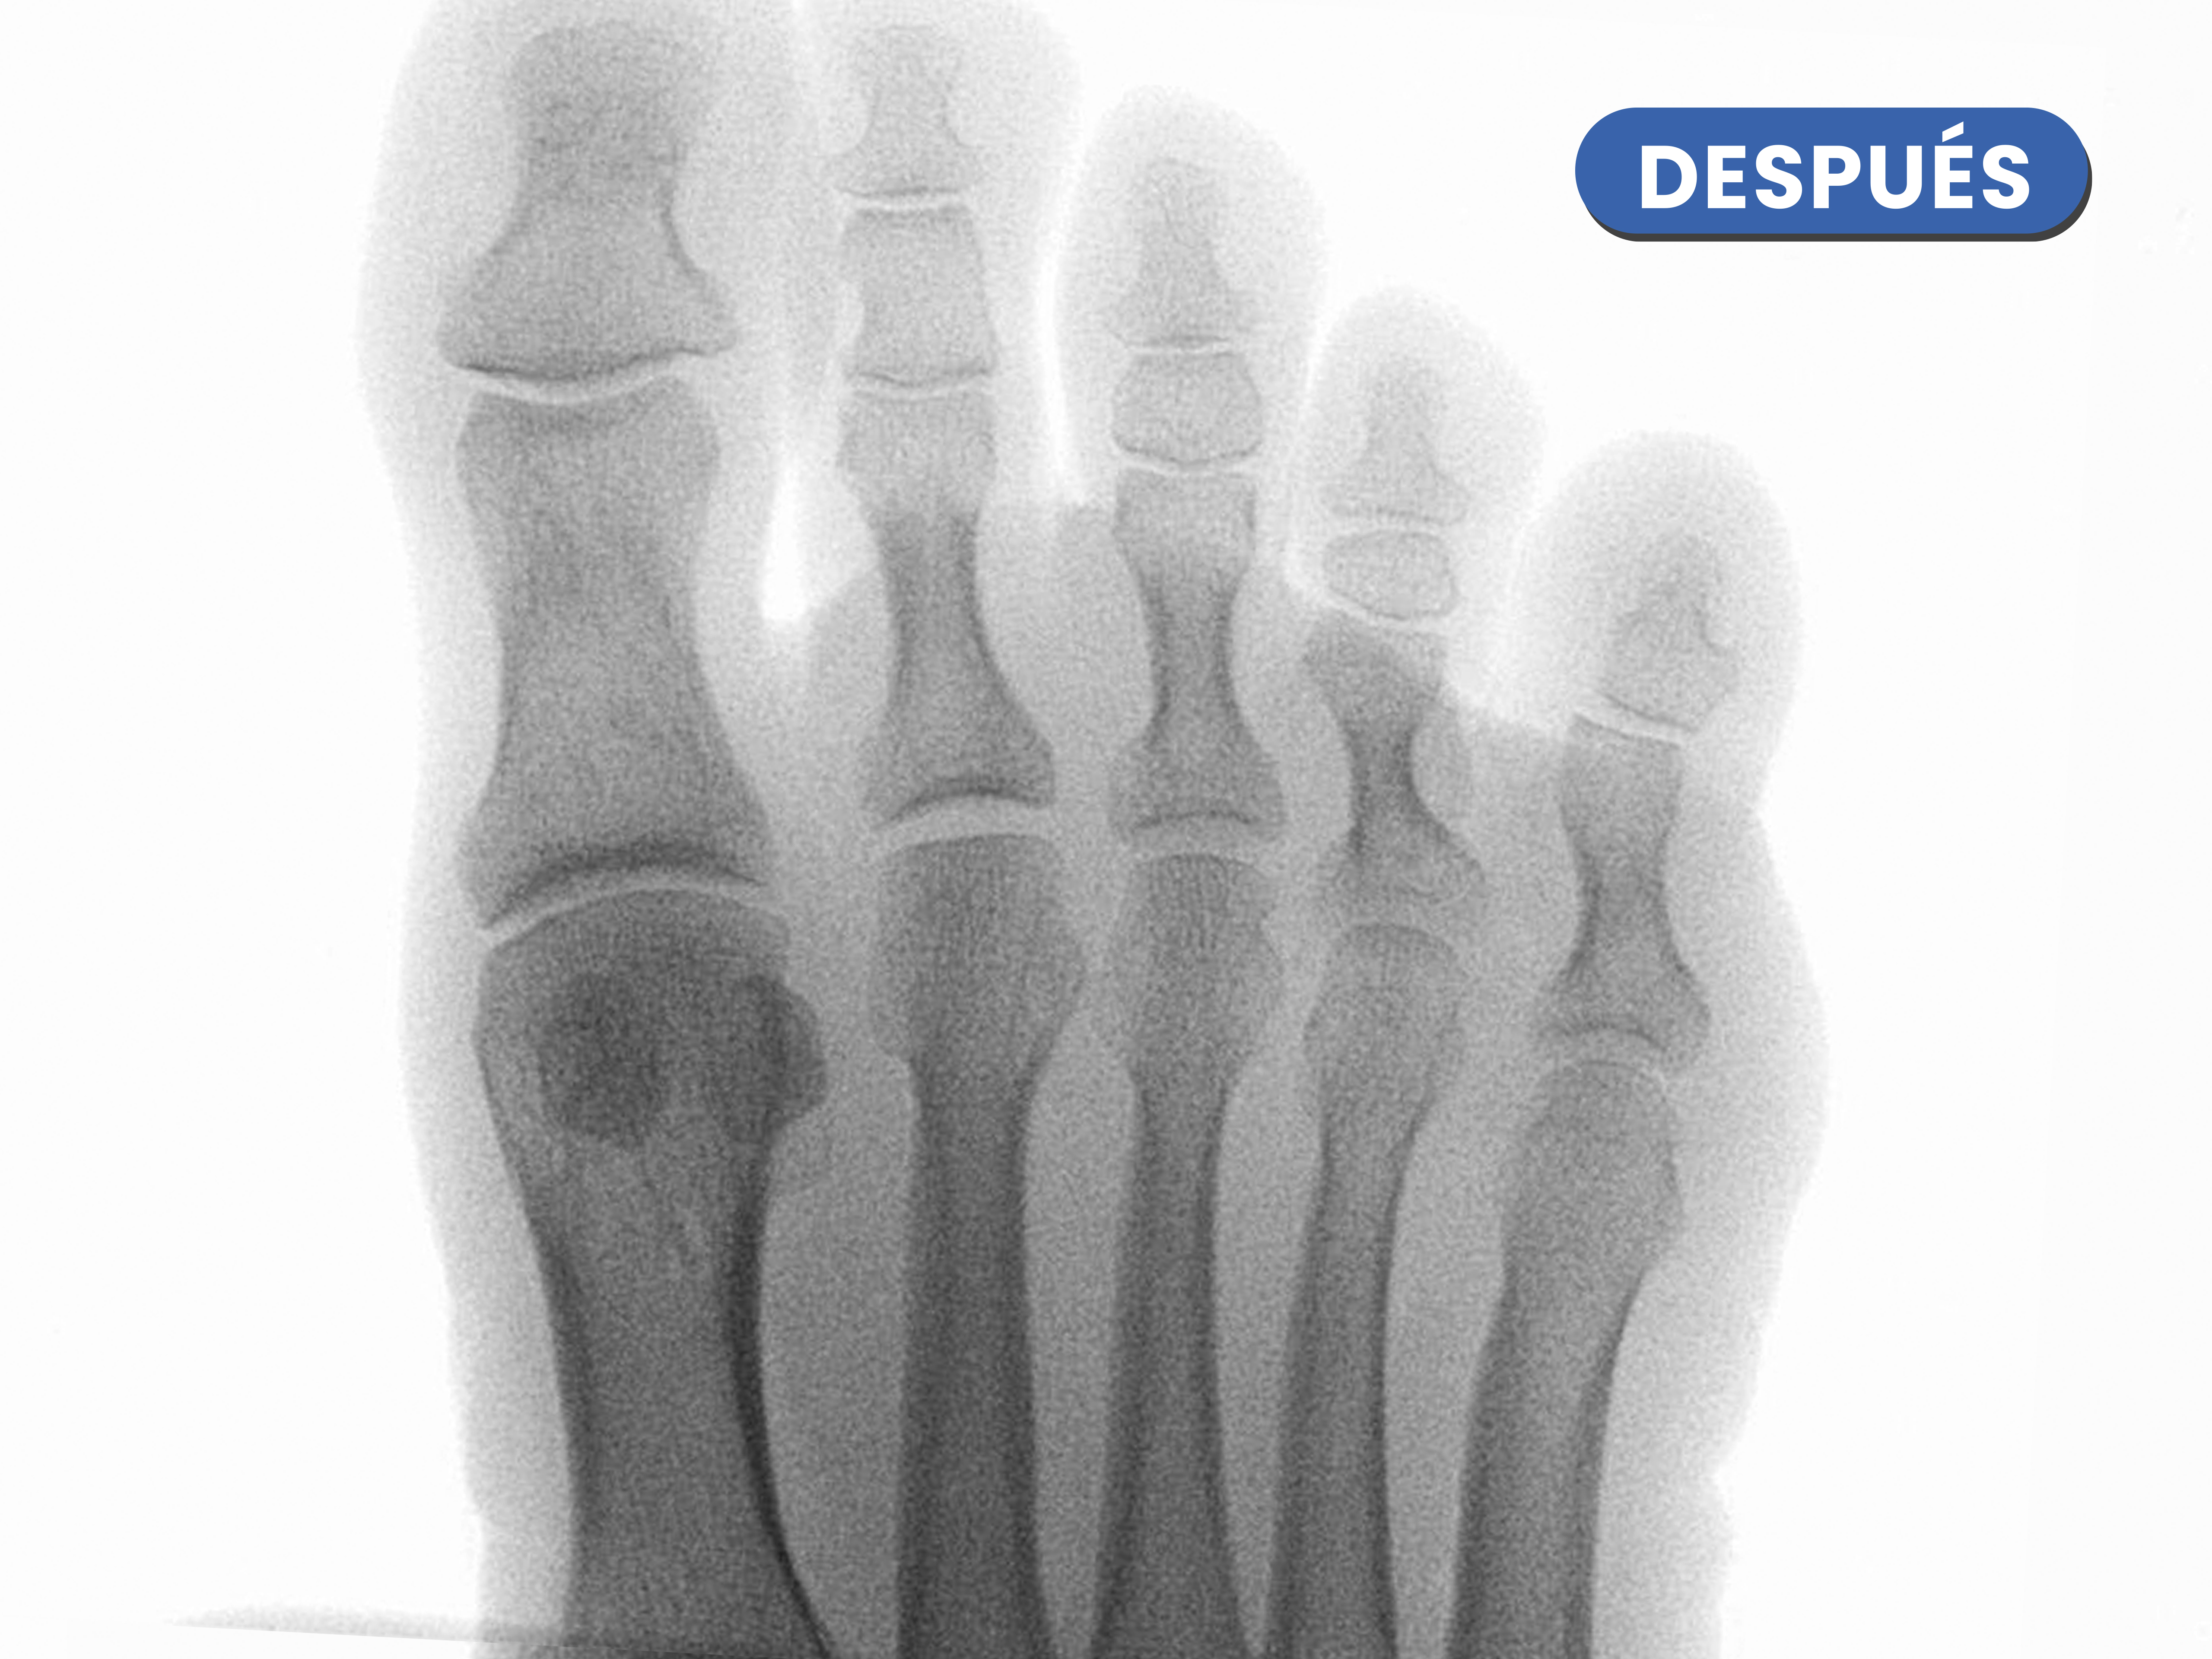

Casos reales resueltos con Cirugía de Mínima Incisión (CMI)

Te mostramos casos reales resueltos mediante cirugía de mínima incisión por el Dr. Rubén Lorca y su equipo.

Mueve las flechas para visualizar el antes y después.

En la radiografía previa a observamos la hipertrofia en la base de la falange distal y la cabeza de la falange proximal como desaparece tras el limado con la fresa.